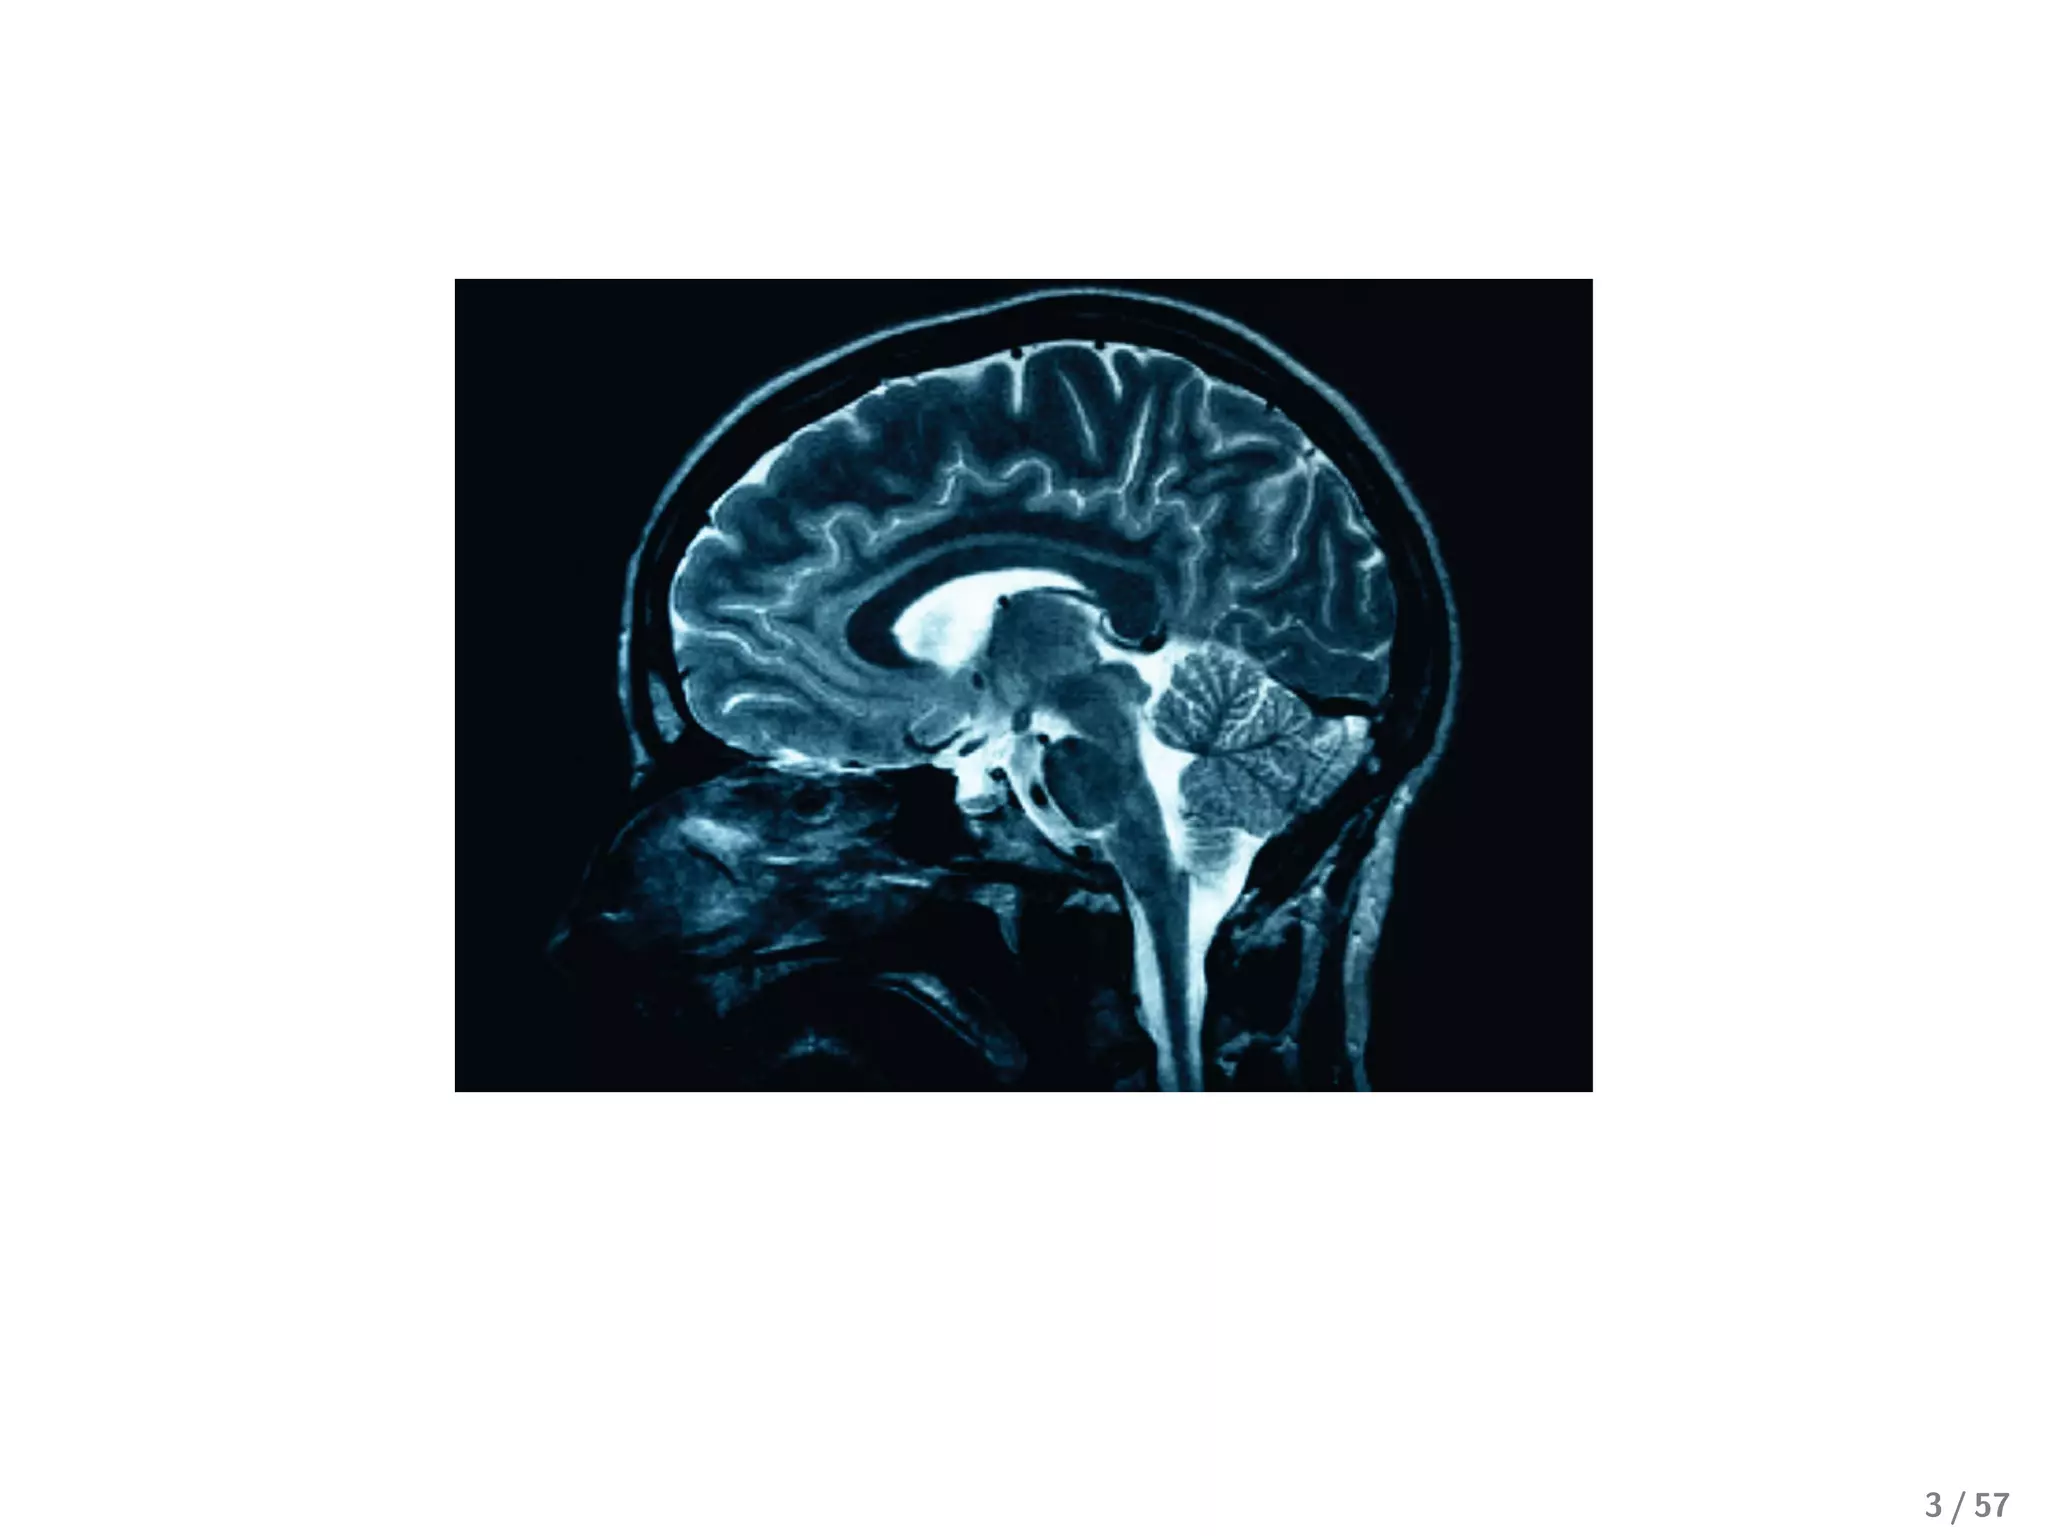

MRI can give us:

High-resolution anatomical images

Real-time measurements of blood flow (fMRI)

13 / 57

A typical MRI experimental data set contains:

10 MB of anatomical data

∼ 1 GB of fMRI data

Time series of blood flow sampled every 2s

Sampled at 60 x 60 x 60 voxels

14 / 57

MRI can giveus: High-resolution anatomical images Real-time measurements of blood flow (fMRI) 13 / 57

• 14.

A typical MRIexperimental data set contains: 10 MB of anatomical data ∼ 1 GB of fMRI data Time series of blood flow sampled every 2s Sampled at 60 x 60 x 60 voxels 14 / 57